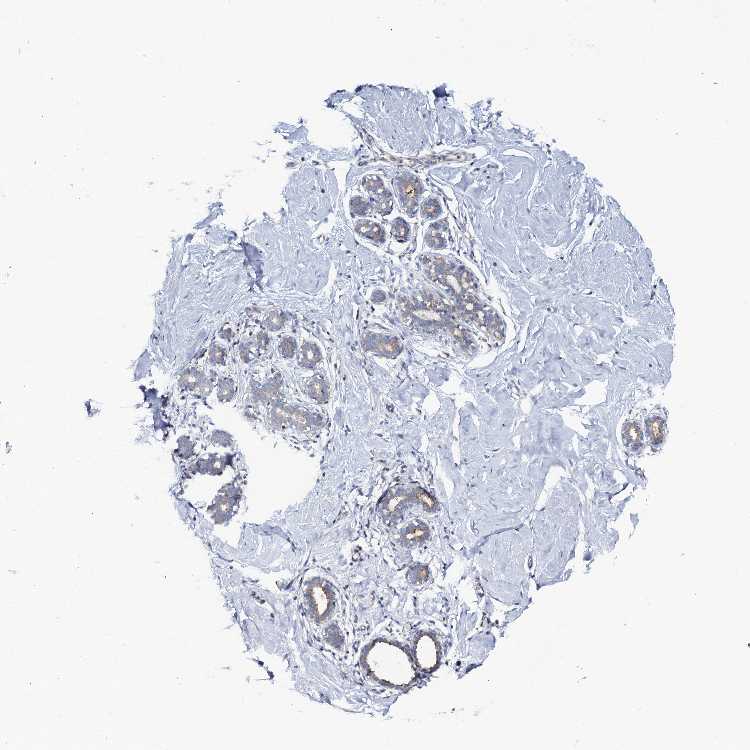

BREAST - Antibody stainingi

Antibody staining in the annotated cell types in the current human tissue is reported as not detected, low, medium, or high, based on conventional immunohistochemistry profiling in selected tissues. This score is based on the combination of the staining intensity and fraction of stained cells.

Each image is clickable and will lead to virtual microscopy that enables deeper exploration of all samples and also displays staining intensity scores, fraction scores and subcellular localization as well as patient and tissue information for each sample.

Antibody HPA041030

Adipocytes Not detected

Glandular cells Low

Myoepithelial cells Not detected